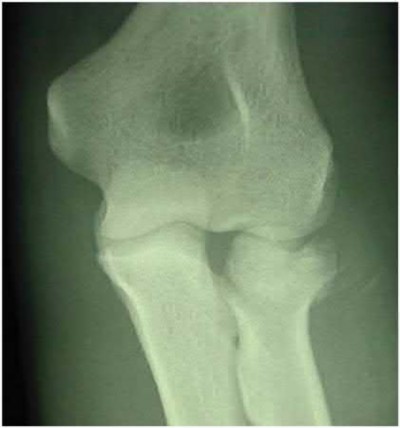

Question 9:

The Lisfranc ligament is the strongest ligament in the tarsometatarsal joint complex. It courses obliquely from the lateral aspect of the medial cuneiform to the medial base of the second metatarsal. It acts as the primary stabilizer of the second metatarsal base. Disruption results in the classic widening between the first and second rays, often with an avulsion fragment ('fleck sign').